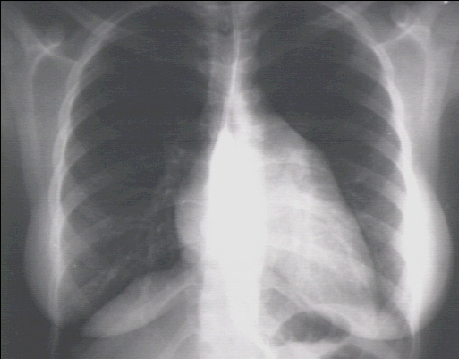

PA

This PA view demonstrates the enlarged left ventricle as an increase in the inferolateral cardiac border associated with an increased cardiothoracic ratio . The markedly enlarged left atrium is manifested by the double contour within the heart border, an elevated left mainstem bronchus and an enlarged , left atrial appendage.